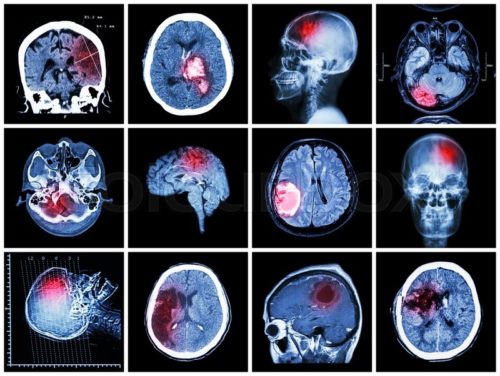

КТ головного мозга

Обследование длится около трех минут, ввести контраст – примерно 20 минут. Предварительная подготовка не требуется, результаты готовы сразу. Пациент получает пошаговые снимки, цельные изображения всех тканей и образований головного мозга. Информацию можно сохранить в цифровом виде для наиболее подробного рассмотрения.

Обследование назначается для определения:

- целостности костной ткани;

- анализа повреждений;

- инородных предметов;

- гематом, кровоизлияний;

- отека мозга после сотрясения;

- нарушений кровообращения;

- абсцессов мозга.

Исследовать можно любой орган, ткань. Снимки необходимы при уточнении диагноза, подозрений. С помощью снимков КТ и контрастного вещества можно рассмотреть изменения в сосудистой системе. Ранние стадии опухолей, инсульта, гематомы, переломы, смещение костей при переломах, расположение осколков, причины увеличения лимфатических узлов. Технология КТ позволяет с большой точностью установить изменения и визуализировать их на компьютере.

Различные структуры отображаются разными цветовыми оттенками. Плотные текстуры имеют белый цвет – они поглощают радио лучи. Мягкие ткани, переломы, не создают проблем для прохождения луча – на пленке отображаются темными пятнами. Процесс съемки занимает около 10 минут, и сразу виден результат. Его можно записать на цифровой носитель, распечатать. Для четкого изображения мягких тканей, жидкости используют краситель, он может вводиться, например, в сустав. Это называется артрограммой. Необходима для изображения расположения иглы в суставе во время дренажа или введения лекарств.